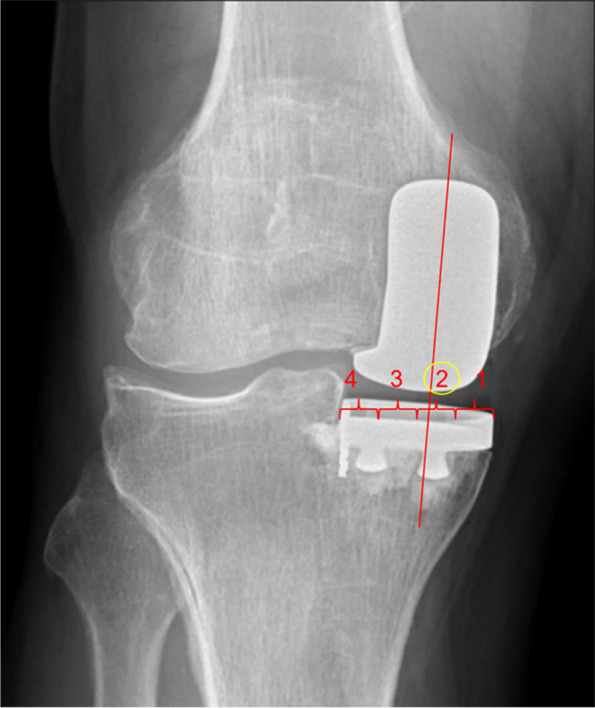

Methods: This retrospective case control study involved 140 UKA (82 C-UKA and 58 R-UKA) performed at an academic institution between March 2016 to November 2020, with a mean follow-up of 3 years. Postoperative radiographs were evaluated for mechanical axis and femoral-tibial component position. Component position was measured by two methods: (1) femoral-tibial component contact point with reference to four medial-to-lateral quadrants of the tibial tray and (2) femoral-tibial component contact point deviation from the center of the tibial tray as a percentage of the tibial tray width. Baseline demographics and complications were recorded.